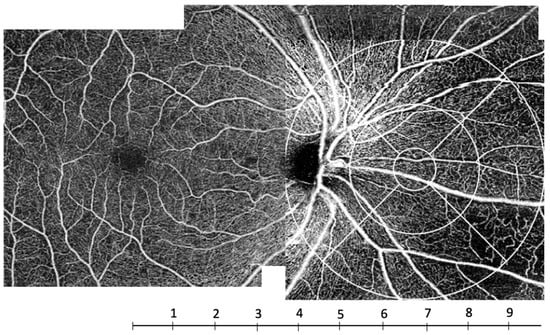

Previous studies have already reported a heterogeneous perfusion on fluorescein angiography and wide-field OCT-A (Figure 7) in diabetic subjects with a predominance of capillary non-perfusion in the mid-peripheral retina [15,16,17]. In 1981, Shimizu et al. used a 130° fluorescein angiography montage technique to show that the extent of capillary non-perfusion in the mid-periphery increased with DR severity. More recently, Alibhai et al. showed a correlation between the mean percentage of non-perfused area and the severity of DR on OCT-A using wide-field 12 × 12-mm images. The mean percentage of non-perfused area was lower in eyes without DR; it increased in eyes with NPDR, and more strongly in eyes with PDR [16].

Figure 7.

OCT-A C-scans of the superficial capillary plexus (SCP). From left to right: examples of a patient without DR, a patient with mild NPDR and a patient with severe NPDR. The vessel density in the SCP progressively decreases with DR severity, especially in the most peripheral area. DR, diabetic retinopathy; NPDR, non-proliferative diabetic retinopathy.

Such a decrease in capillary density in the periphery has already been described in healthy subjects. Carlo Lavia et al. have shown a decreased density in the periphery of the SCP at about 8 mm from the fovea in healthy subjects. This location corresponds to the area where the intermediate capillary plexus vanishes in the periphery [21]. This threshold of 8 mm (about 8 mm temporally and 10 mm nasally, if the optic nerve head is not taken into account) corresponds to zones 6, 7 and 8 of the grid used in our study (Figure 8), that is, the outermost zones of the ETDRS grid moved nasally (Figure 2 and Figure 8). Thus, this peripheral zone could be more vulnerable to ischemia.

Figure 8.

OCTA C-scan montage of the superficial capillary plexus (SCP) in a subject with severe non-proliferative diabetic retinopathy. The scale under the image indicates the distance to the fovea in millimeters. The capillary rarefaction predominated at a distance of about 8 mm from the fovea corresponding to zones 6, 7 and 8.

This heterogeneity of retinal perfusion seems to be comparable to that of the neuronal tissue. The density in the different capillary plexuses indeed correlates with the neuronal volume, the thickness of the cell layers and the metabolic activity of the tissue, which decreases with the distance from the fovea [22]. Interestingly, in our study, there was a significant relationship between vascular density and the severity of DR in the peripapillary areas (zone 4 of the nasal grid and zone 8 of the macular grid). These areas correspond to the areas where the radial peripapillary capillary plexus (RPCP) is present. The RPCP is not individualized by Cirrus segmentation, but it is localized in the optic fiber layer that is included in the segmentation of the SCP. The reduction in RPCP during DR progression has been assessed in previous studies [23,24].